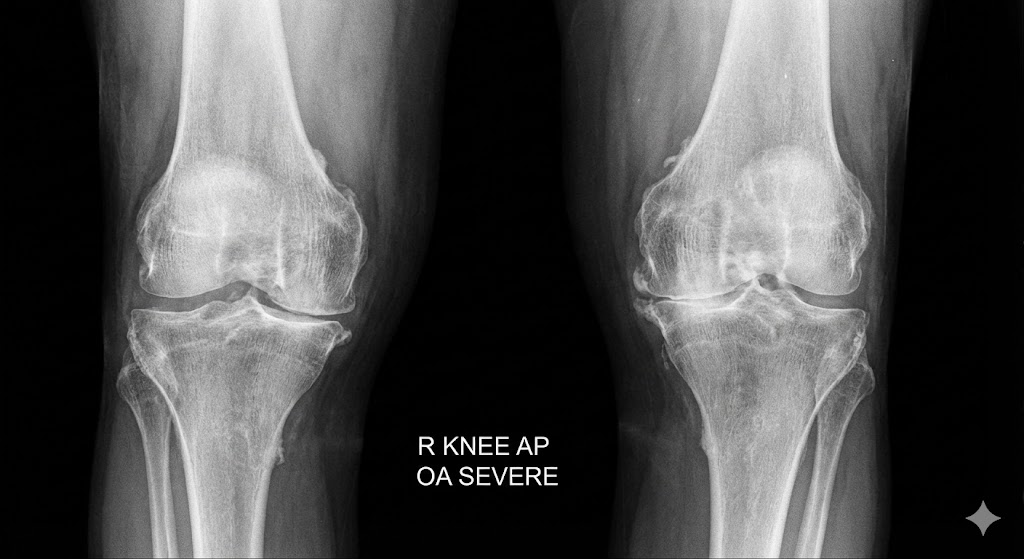

「病院でレントゲンを見せられ、『軟骨がなくなっています』と言われた」

「膝に痛みが”全くない”健康な高齢者」のレントゲンを撮っても、その大多数に「骨の変形」や「軟骨のすり減り」が見つかるのです。

レントゲンで「変形性膝関節症」と診断されるほどの変形がある人のうち、実際に痛みを感じているのは「15%〜81%」と幅がある(研究によっては、変形がある人の85%が無症状というデータもある)。

結論: レントゲン上の変形と、患者が感じる痛みには「明確な不一致」が存在する。変形があるからといって、必ずしも痛むわけではない。

BMC Musculoskeletal Disorders, 2008 Bedson J, Croft PR.

これは、どういうことでしょうか? 「軟骨がすり減っている(構造)」から、「必ず痛い(症状)」わけではない、ということです。 (→腰痛でも同じことが言えます。詳しくはヘルニアが治らない理由の記事もご参照ください)